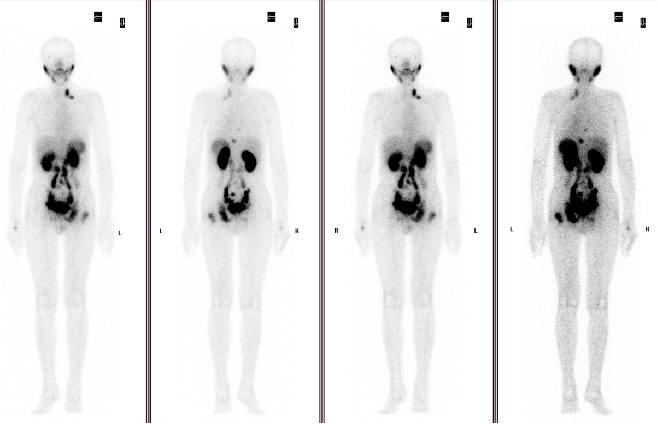

发布高建英主任petct在肿瘤远处转移中的临床应用

图片尺寸960x720